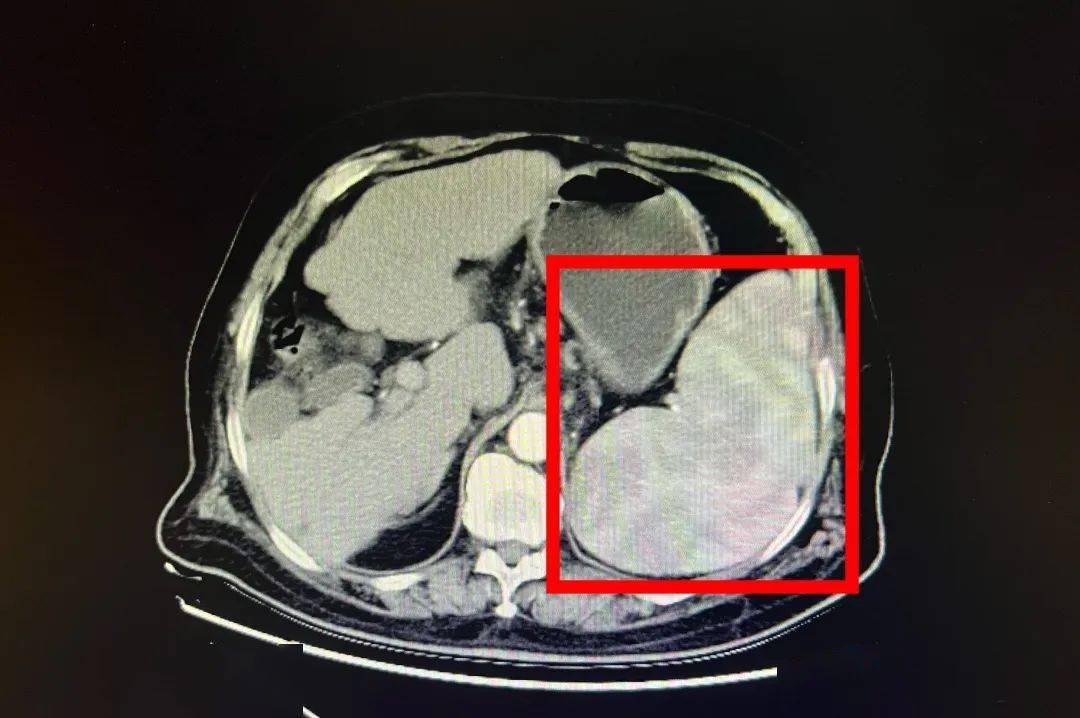

脾脏特别大父母带她到医院检查头晕,头痛,乏力等症状经常出现血小板很

特发性血小板减少性紫癜 部分血小板减少患者会发生脾肿大现象,这

脾肿大是一种常见的医学症状,通常是由于脾脏的体积增大而引起的.